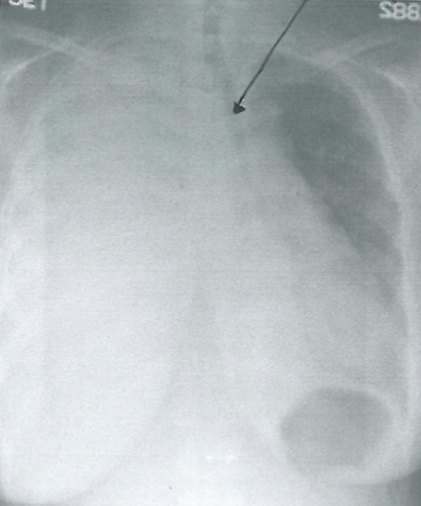

Rx toracică, incidență P-A

DESCRIERE:

la niv. întregului hemitorace stg → opacitate extinsă, nesistematizată, de intensitate mare, omogenă

caracter retractil → tracționează traheea și mediastinul de partea afectată

fără bronhogramă aerică

duce la micșorarea spațiilor intercostale

la niv. hemitoracelui controlateral → hipertransparență compensatorie (emfizem)

DX: atelectazie prin NBP central endobronșic (pe bronhia principală stg)

DD: pleurezie masivă → caracter expansiv